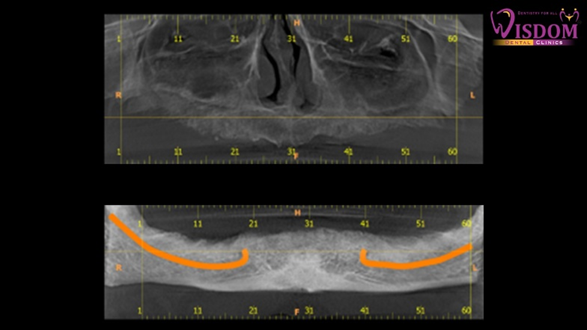

A complete case history was recorded following by thorough intraoral examination. Patient was adviced to undergo routine blood investigation, OPG and CBCT. [Figure 2a,2b]. Going through radiographical and clinical examination full mouth rehabilitation was planned with placement of short and bone level implants with final delivery of hybrid denture in order to get satisfactory results.

Figure 2b: CBCT